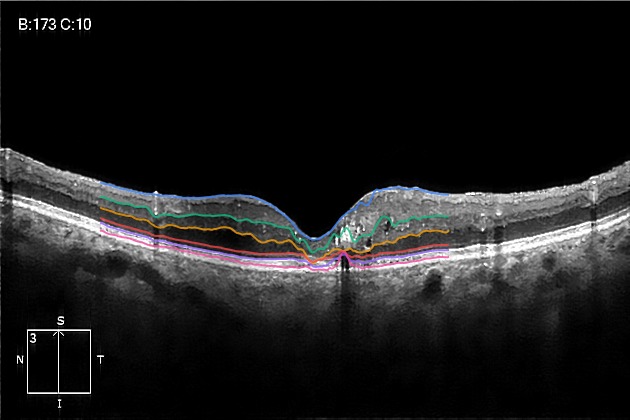

This research proposes a column-wise intensity-based deep learning approach for retinal OCT layer segmentation, using denoising, CNN-BiLSTM modeling, and custom loss functions to accurately detect and reconstruct six retinal layers. The lightweight model is optimized for deployment on edge devices while maintaining high accuracy in medical image analysis.